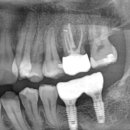

10년 이상 협업 중인 디지털 기공소와 함께 모든 케이스를 정밀하게 제작합니다. 즉, 보험이 적용되는 경우라도 기성 어버트먼트를 사용하는 일은 없습니다.이로운치과 임플란트 왜 이렇게까지...

임플란트 하나를 심더라도 최선을 다하는 원주 혁신도시, 관설동 이로운치과 입니다. 오늘은... 전문 기공소와 협업하여 심미적이고 기능적인 치아를 제작하는 데 최선을 다하고 있습니다. 인싸력이...